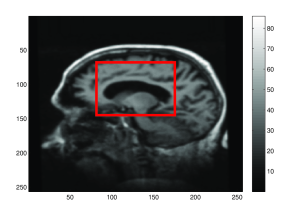

In this paper, we use higher-order momentum distributions in the LDDMM registration framework to obtain a deformation parametrization that increases the capacity of sparse approaches with a basis consisting of interpretable elements. We show how the higher-order representation model locally affine transformations, and we use the compact deformation description to register points and images using very few parameters. We illustrate how the deformation coded by the higher-order momenta can be directly interpreted and that it represents information directly useful in applications: with low numbers of control points, we can detect the expanding ventricles of the patient shown in Figure 1.

Refer to caption

(b) Follow up (box marking zoom area, figure (c) and (d)).

Fig. 1: Progressing Alzheimer’s disease cause atrophy and expansion of the ventricles. By placing five deformation atoms in the ventricle area of the baseline MRI scan [20] and by using higher-order momenta, we can detect the expansion. (a) The position of the deformation atoms shown in the baseline scan; (b) the follow up scan; (c) the log\log-Jacobian determinant of the generated deformation in the ventricle area (red box in (b)); (d) the vector field at t=0𝑡0t=0 of the generated deformation. The logarithm of the Jacobian determinant and the divergence at the deformation atoms are positive which is in line with the expected ventricle expansion, confer also Figure 7.